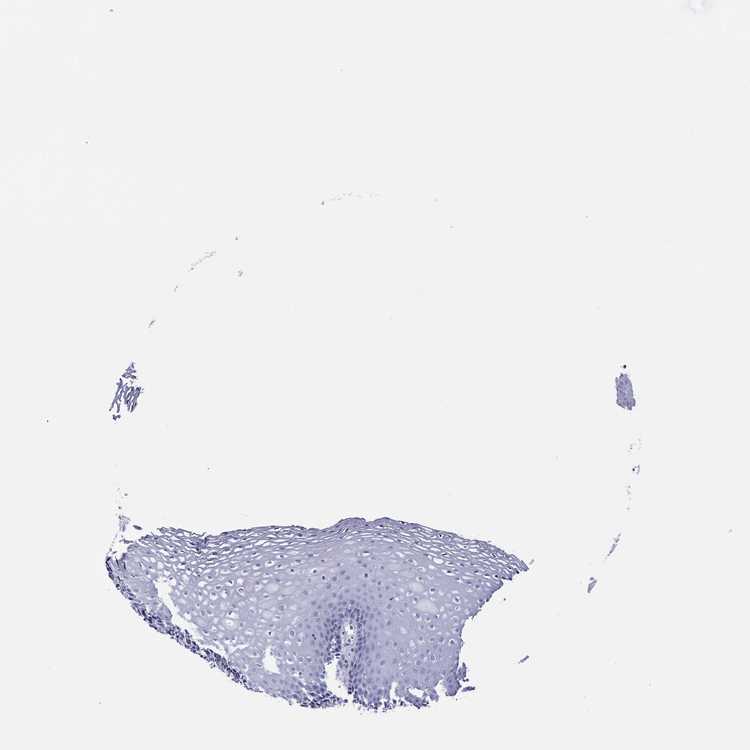

ESOPHAGUS - Antibody stainingi

Antibody staining in the annotated cell types in the current human tissue is reported as not detected, low, medium, or high, based on conventional immunohistochemistry profiling in selected tissues. This score is based on the combination of the staining intensity and fraction of stained cells.

Each image is clickable and will lead to virtual microscopy that enables deeper exploration of all samples and also displays staining intensity scores, fraction scores and subcellular localization as well as patient and tissue information for each sample.

Antibody HPA012911

Squamous epithelial cells Not detected